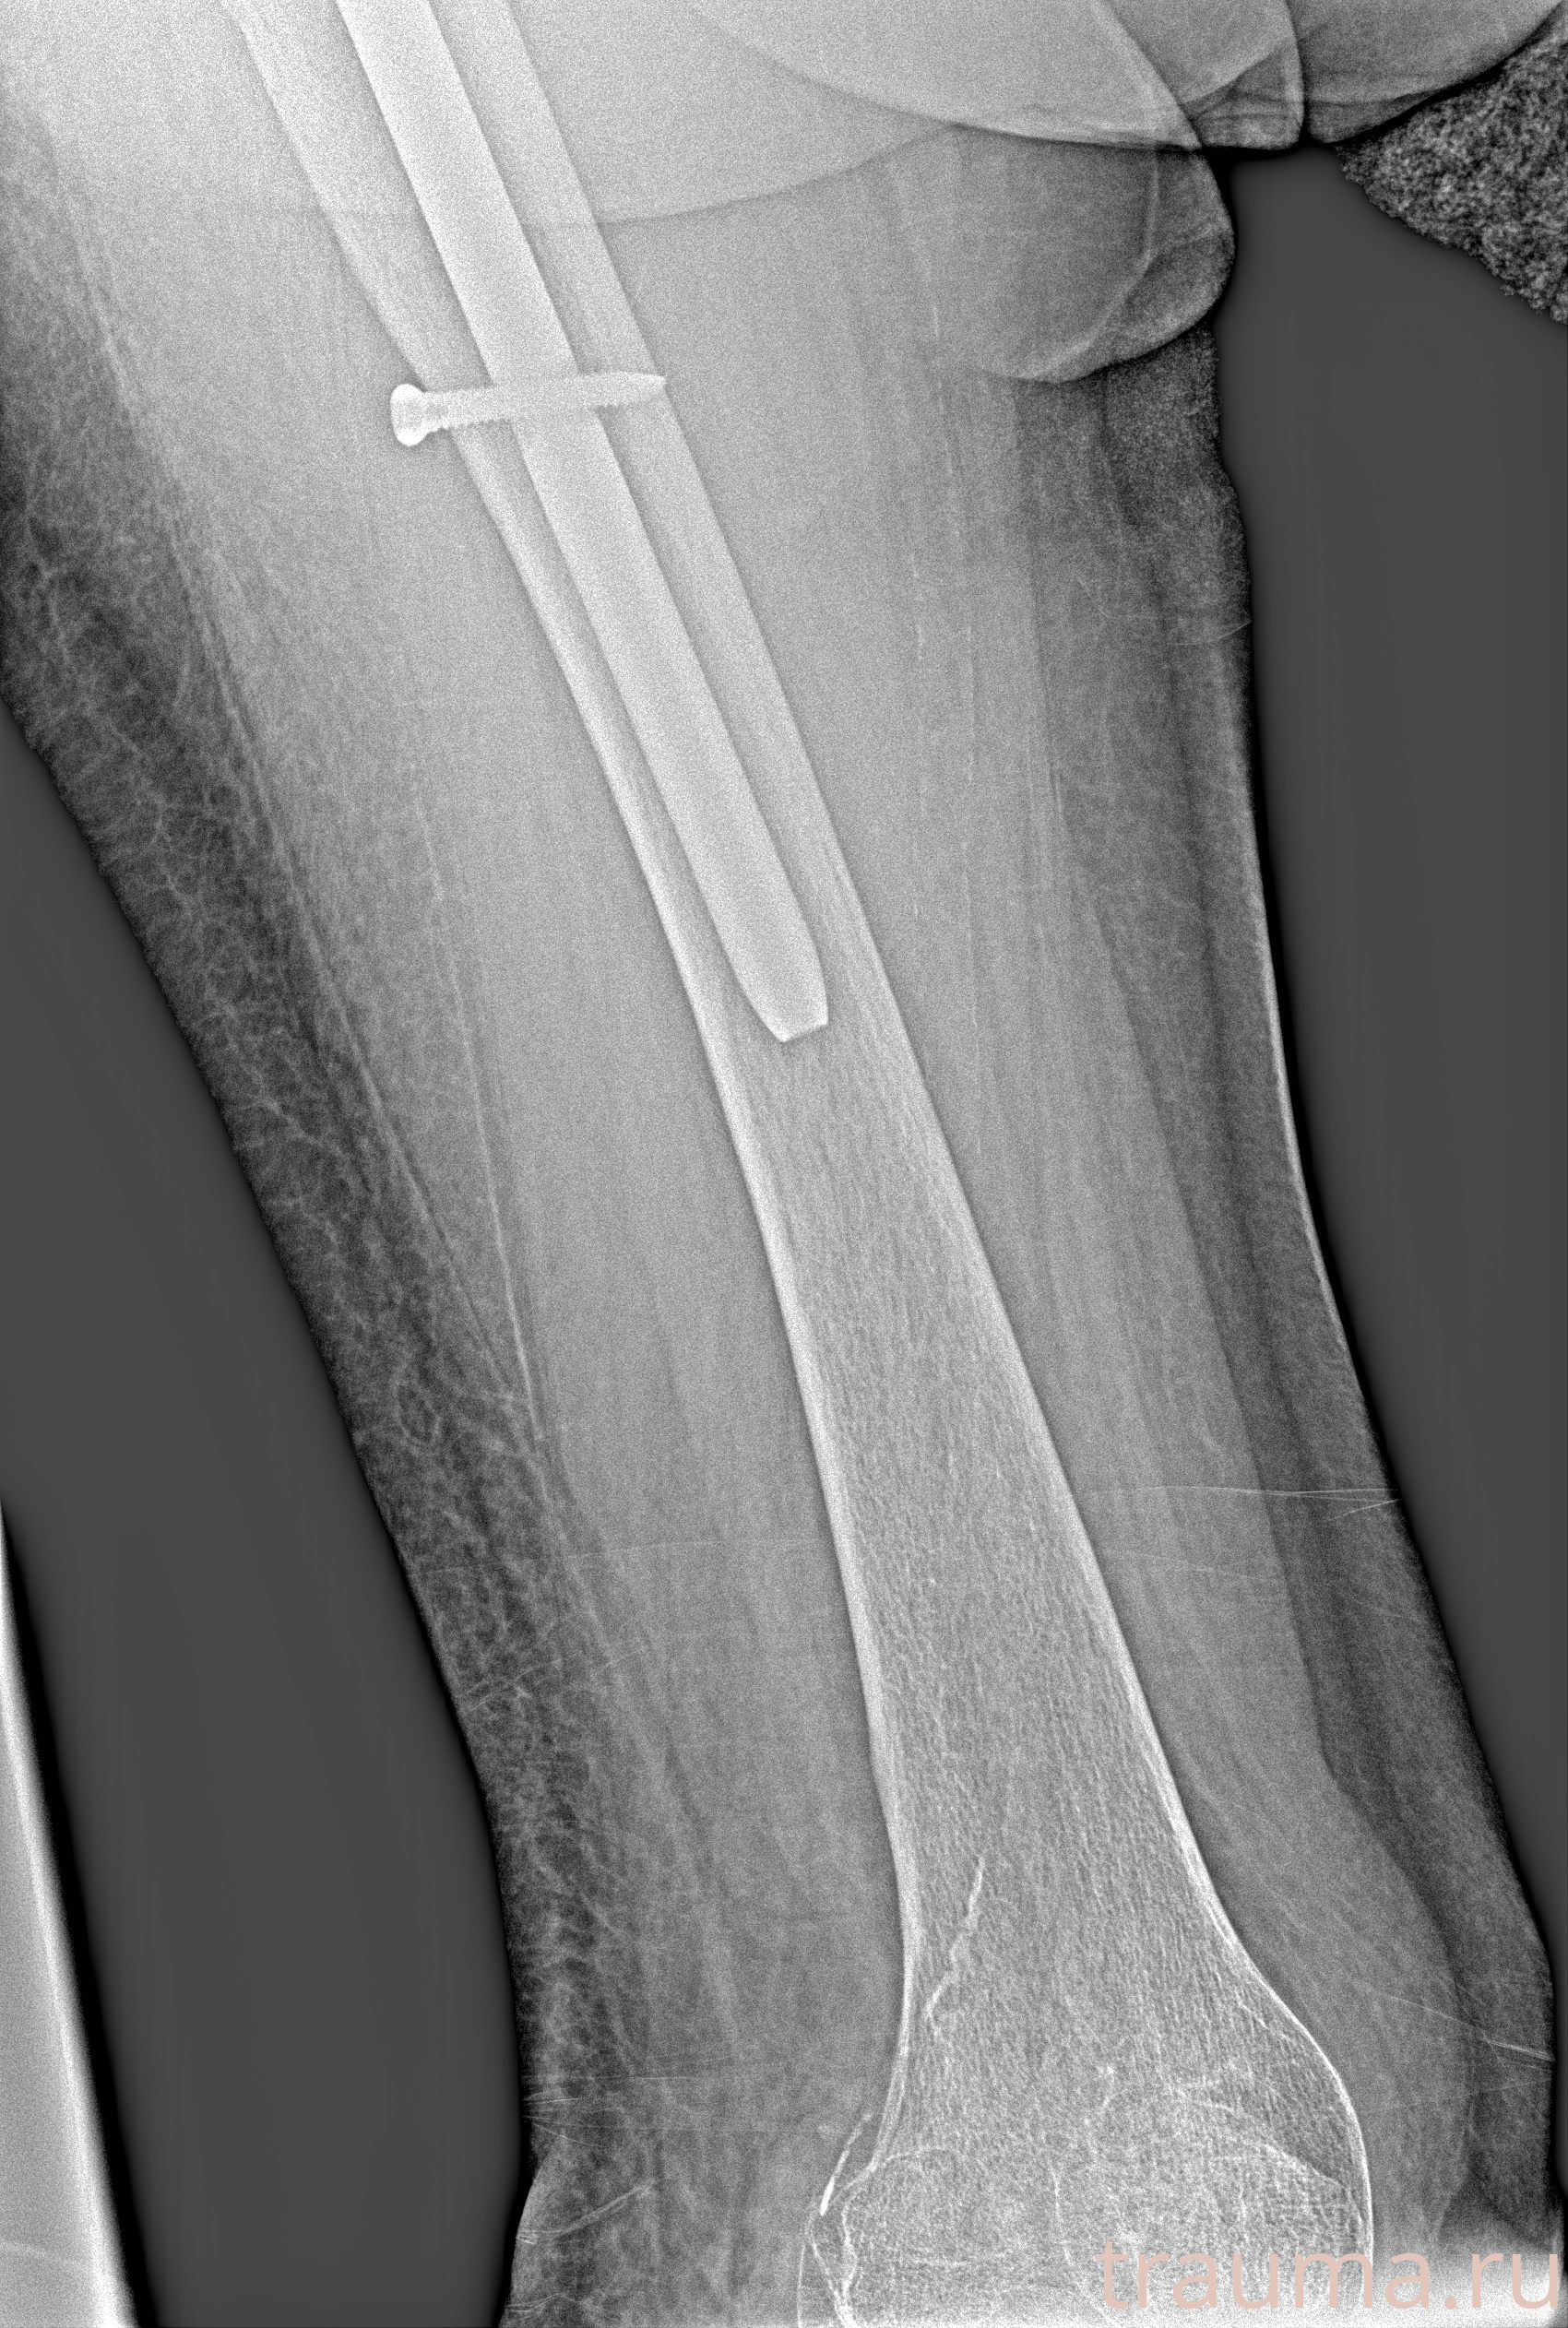

Рентген на дому: по вашему адресу приезжает врач-рентгенолог, травматолог-ортопед с мобильным рентгеновским аппаратом, проводит диагностику травмы или заболевания, делает необходимые рентгенограммы, дает рекомендации по дальнейшему лечению. Получить качественные снимки в домашних условиях возможно благодаря уникальной методике, разработанной МосРентген Центром для института  Склифосовского